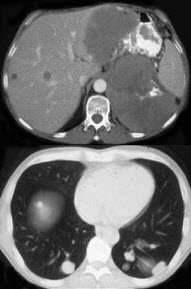

女,38岁,低热乏力并消瘦2月余,CT如图所示,下列说法正确的是( )

A:左侧肾上腺区巨大的占位性病灶考虑为肾上腺癌

B:左侧肾上腺区巨大的占位性病灶考虑为嗜铬细胞瘤

C:左侧肾上腺区巨大的占位性病灶考虑为肾上腺腺瘤

D:肺内多发小结节病灶,考虑为肺转移瘤

E:肺内多发小结节病灶,考虑为肺结核